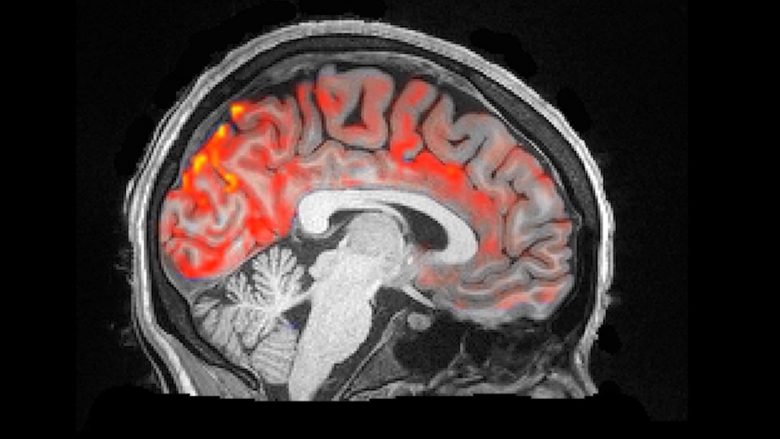

Mbase këtë nuk e keni ditur, mirëpo organizmi ynë çdo natë shpëlan trurin tonë

Neuro-shkencëtarët kanë bërë xhirim të mrekullueshëm në të cilin shihet pastrimi pulsues i aparatit tonë të trurit, shkruan Science Alert.

Sipas hulumtimit më të ri, gjatë natës nëpër trurin tonë rrjedhin valët e lëngut cerebrospinalë, duke pulsuar ritmikisht derisa ne flemë gjumë dhe eliminojnë toksinën e dëmshme.

Lëngu cerebrospinal plotëson hapësirën përreth trurit dhe palcës kurrizore dhe i mbron nga prekja e drejtpërdrejtë me kafkën përreth trurit.

“Tashmë një kohë të gjatë e dimë që në neurone ekzistojnë valë të aktiviteteve elektrike. Mirëpo, sapo i kemi vërejtur valët në lëngun cerebrospinal”, ka thënë neuro-shkencëtarja Lora Lusi nga Universiteti i Bostonit.

Duke pasur parasysh që gjatë procesit të plakjes bie frekuenca e ngadalshme e valëve të trurit, ky studim më i ri do të mundë të ndihmojë me rastin e hulumtimit të problemeve të lidhura me plakjen, bashkë me çrregullimet specifike karakteristike për moshën vjetër.